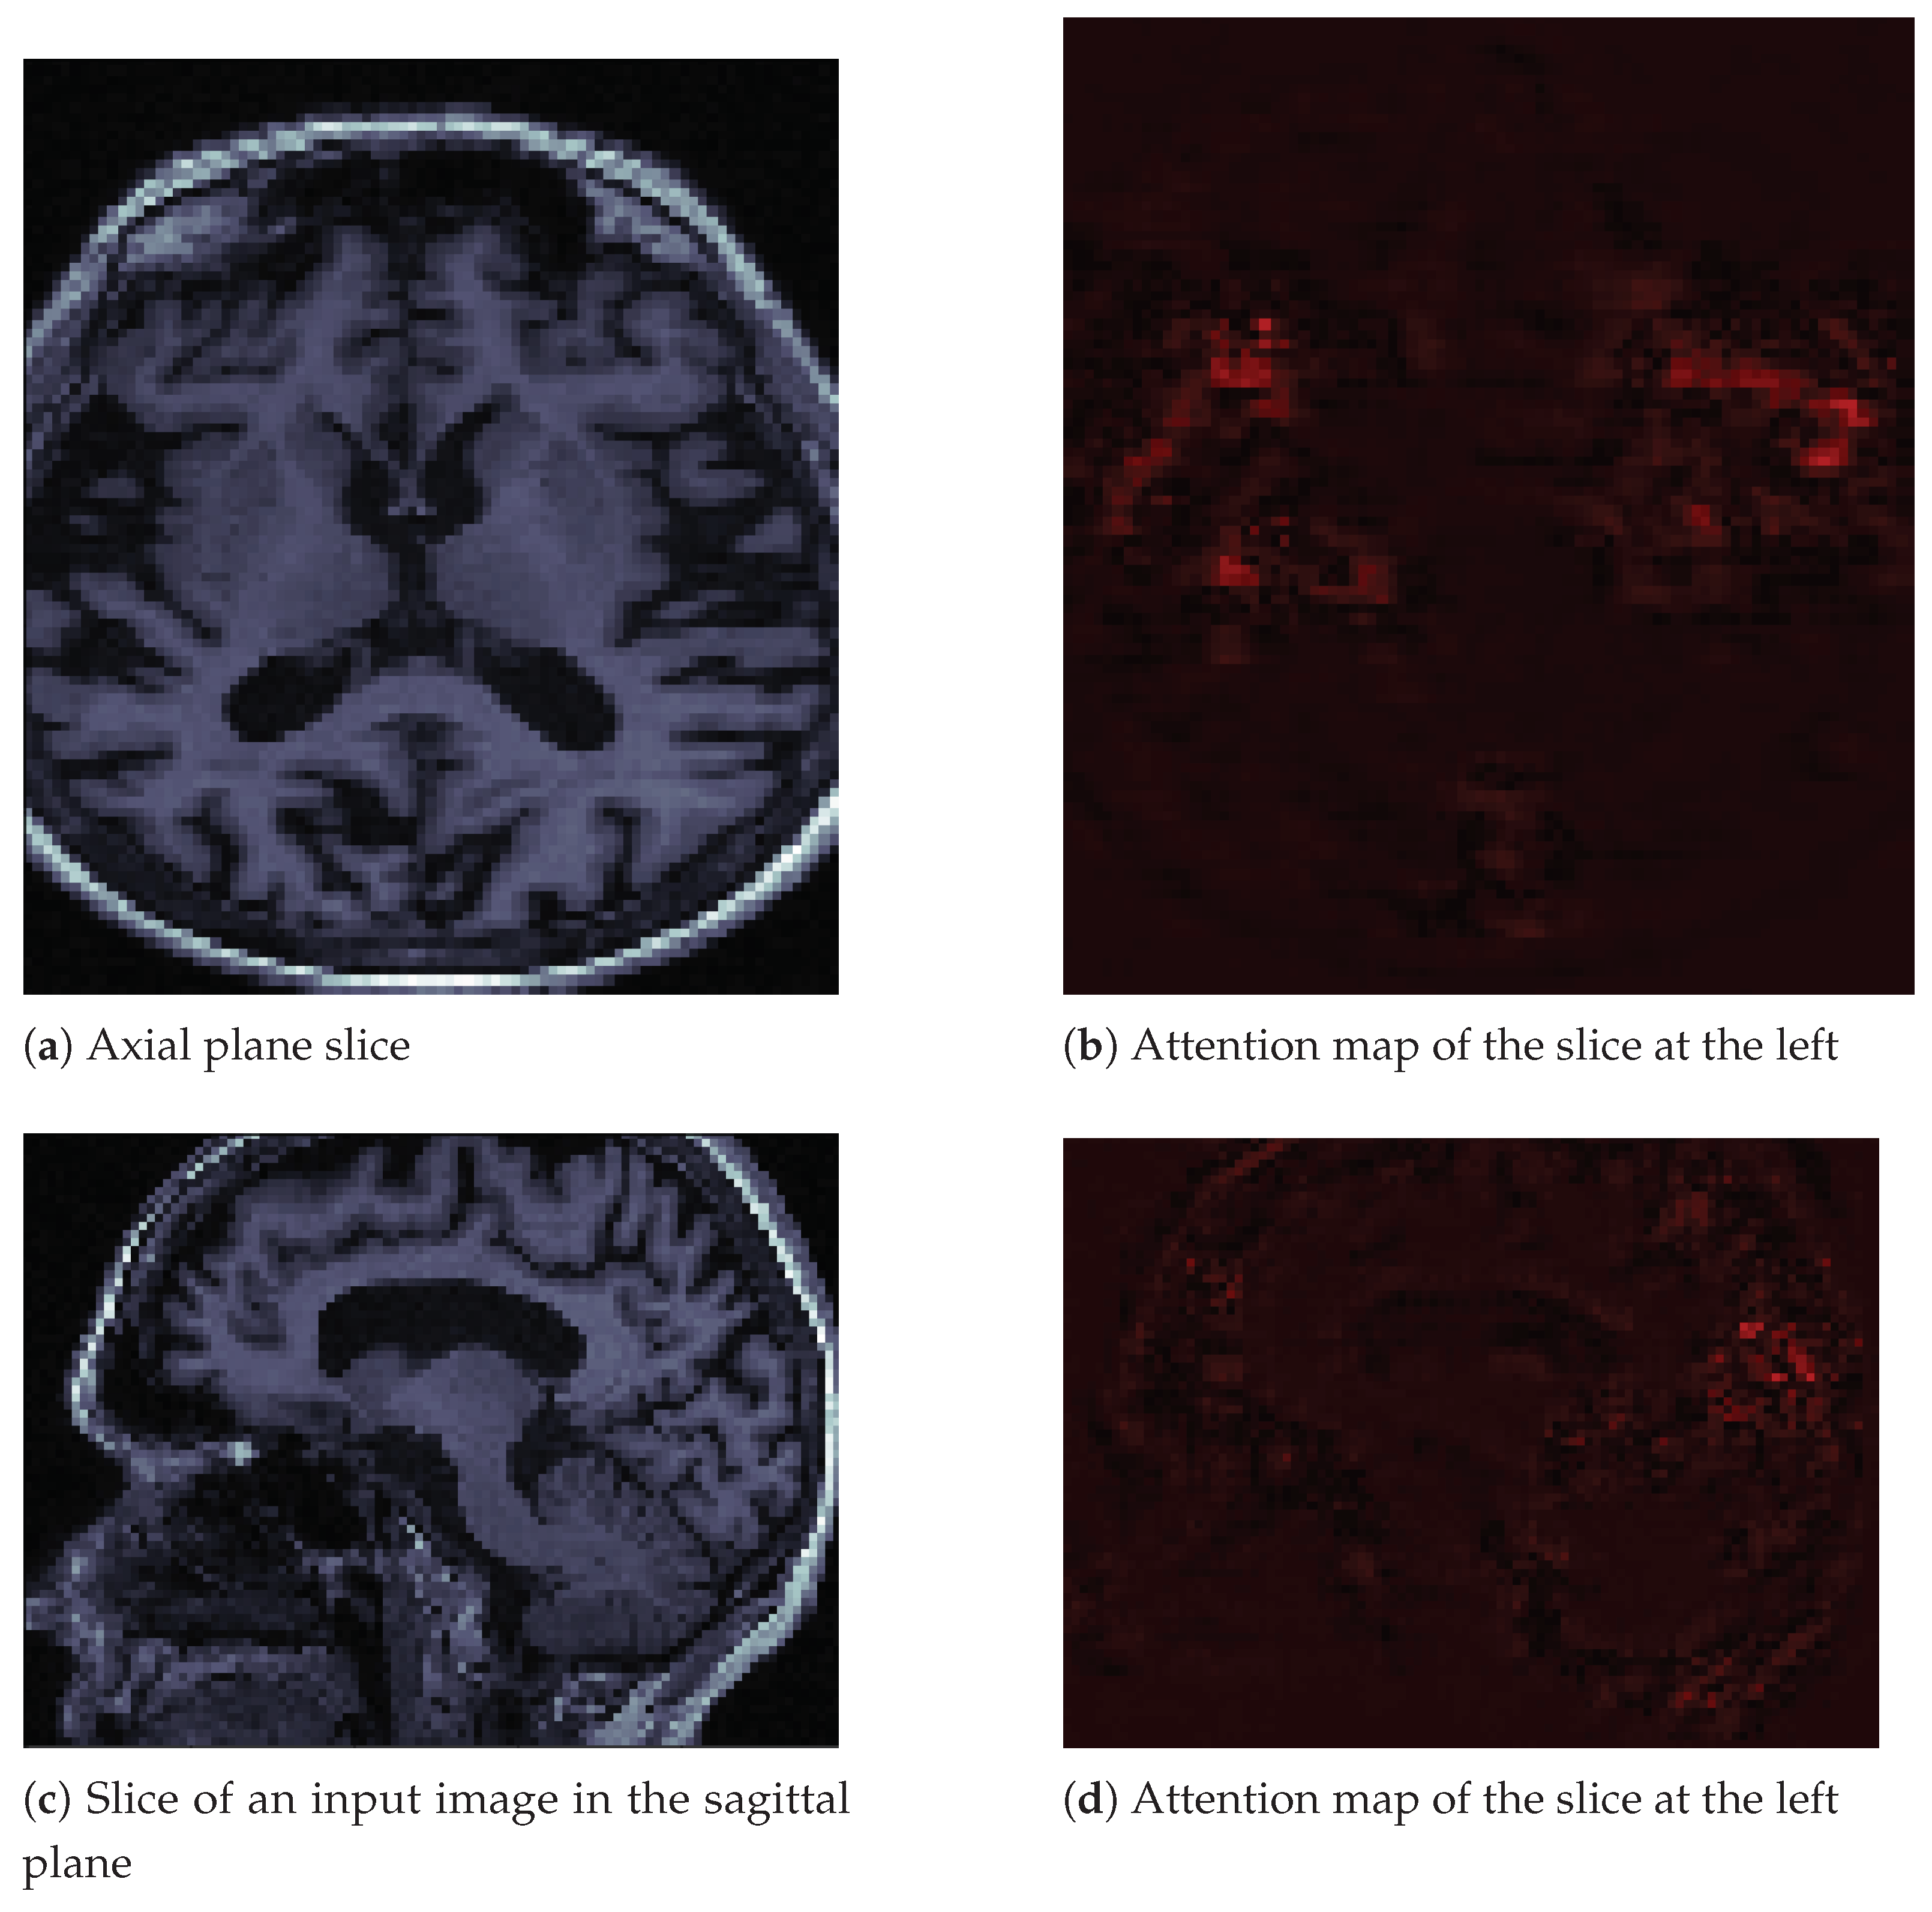

Attention maps are visual tools that explain deep convolutional neural networks [33]. We used the M3d-Cam tool [34] with the Guided Gradient-weighted Class Activation Mapping (Grad-CAM) algorithm. We generated new images through M3d-CAM, and with these images, we could interpret what the neural network was emphasizing to make a decision. For example, in Figure 6a, we can see an image in the axial plane of a person with Alzheimer’s disease. We extracted only one slice of the cuboid. To its right, in Figure 6b, we can see that the neural network focuses its attention on brain atrophy. We extracted the same slice number from the attention map cuboid. In Figure 6c,d, we see the same patient and the same features in the sagittal plane. We also only extracted one slice of that plane.

In the images in Figure 6, we can see how brain atrophy areas appear more prominent. We noticed this behavior in other images for which we produced attention maps. The behavior of the network was as expected in terms of identifying the regions of importance. However, we also noticed that sometimes the neural network gave importance to bony areas of the skull or even to areas outside the skull. In other words, the attention maps seemed to have a potential function as debugging tools. Besides, they allowed us to propose solutions. We believe that we must improve the preprocessing of images by removing the skull using a mask, as the skull is a potential source of noise. This background noise could explain some of the classifier’s inaccurate results, as observed in the confusion matrices. The neural network may be learning uninformative features or patterns as a result of excess inputs. We could improve the results and reduce the inaccurate results by providing the CNN with only brain images, thus removing potential artifacts associated with the skull.

Additionally, we include the attention map for a non-affected individual in Figure 7 on page 14. The difference from the image in Figure 6 is that this image seems to generate less attention from the neural network. We observed the same behavior in other images of healthy people.

Figure 6. Input image slices and their attention maps from an MRI of a patient with AD.